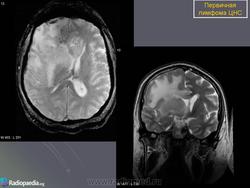

Первичные лимфомы ЦНС. Вс, 22/05/2011 - 21:45 #1 Катенёв Валенти... Не на сайте Был на сайте: 7 лет 5 месяцев назад Зарегистрирован: 22.03.2008 - 22:15 Публикации: 54876 Продолжение.Приложения: